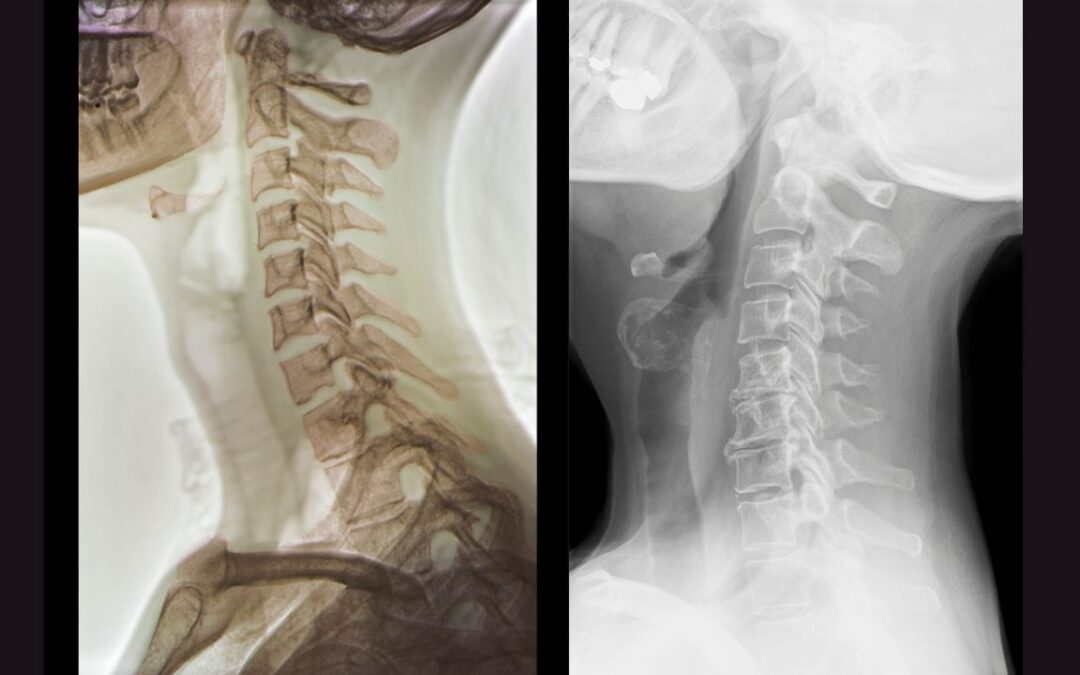

Understanding Cervical Spondylosis: How Chiropractic Care Can Offer Relief In today’s fast-paced world, many of us find ourselves spending prolonged hours at our desks, whether it’s toiling away on computers, managing paperwork, or even engaging in...

Understanding Cervical Disc Herniation: A Comprehensive Guide to Relief through Chiropractic Care Introduction: In today’s fast-paced world, many of us spend hours seated at desks or engaging in physically demanding jobs. Whether you’re an IT professional,...

Understanding Whiplash-Associated Disorders: How Chiropractic Care Can Help Introduction: Whiplash-associated disorders (WAD) are a common consequence of vehicular accidents, often resulting in significant discomfort and impairment for those affected. As professional...

Understanding and Addressing Cervicogenic Headaches: A Guide to Chiropractic Care Introduction: In today’s fast-paced world, professional individuals often find themselves burdened with various stressors, deadlines, and responsibilities. Amidst these challenges,...

Understanding Cervicalgia: A Comprehensive Guide to Chiropractic Care Introduction: Neck pain, medically termed cervicalgia, is a prevalent condition that affects countless individuals worldwide. Whether it stems from poor posture, injury, or underlying medical...